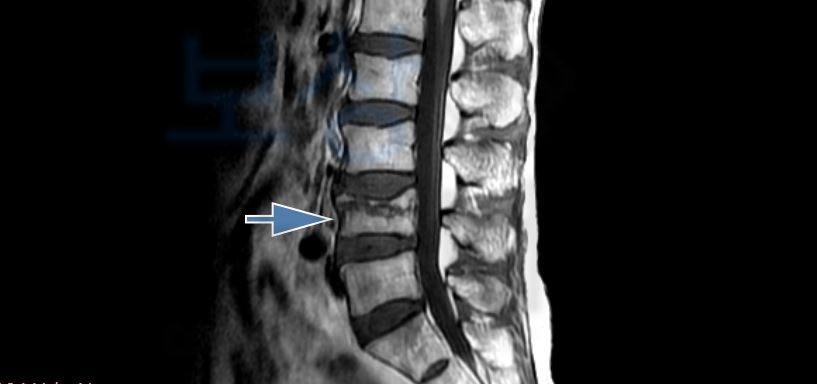

골절의 모습이 좋지않아 추후 큰 후유증을 야기할 수 있어 골시멘트술을 받으셨는데요, 조@@님께서 받은 시술은

골절된 척추체를 목표로

의료용 시멘트를 주사하는

척추의 안정성을 위한 시술입니다. 골시멘트시술을 받은 이후